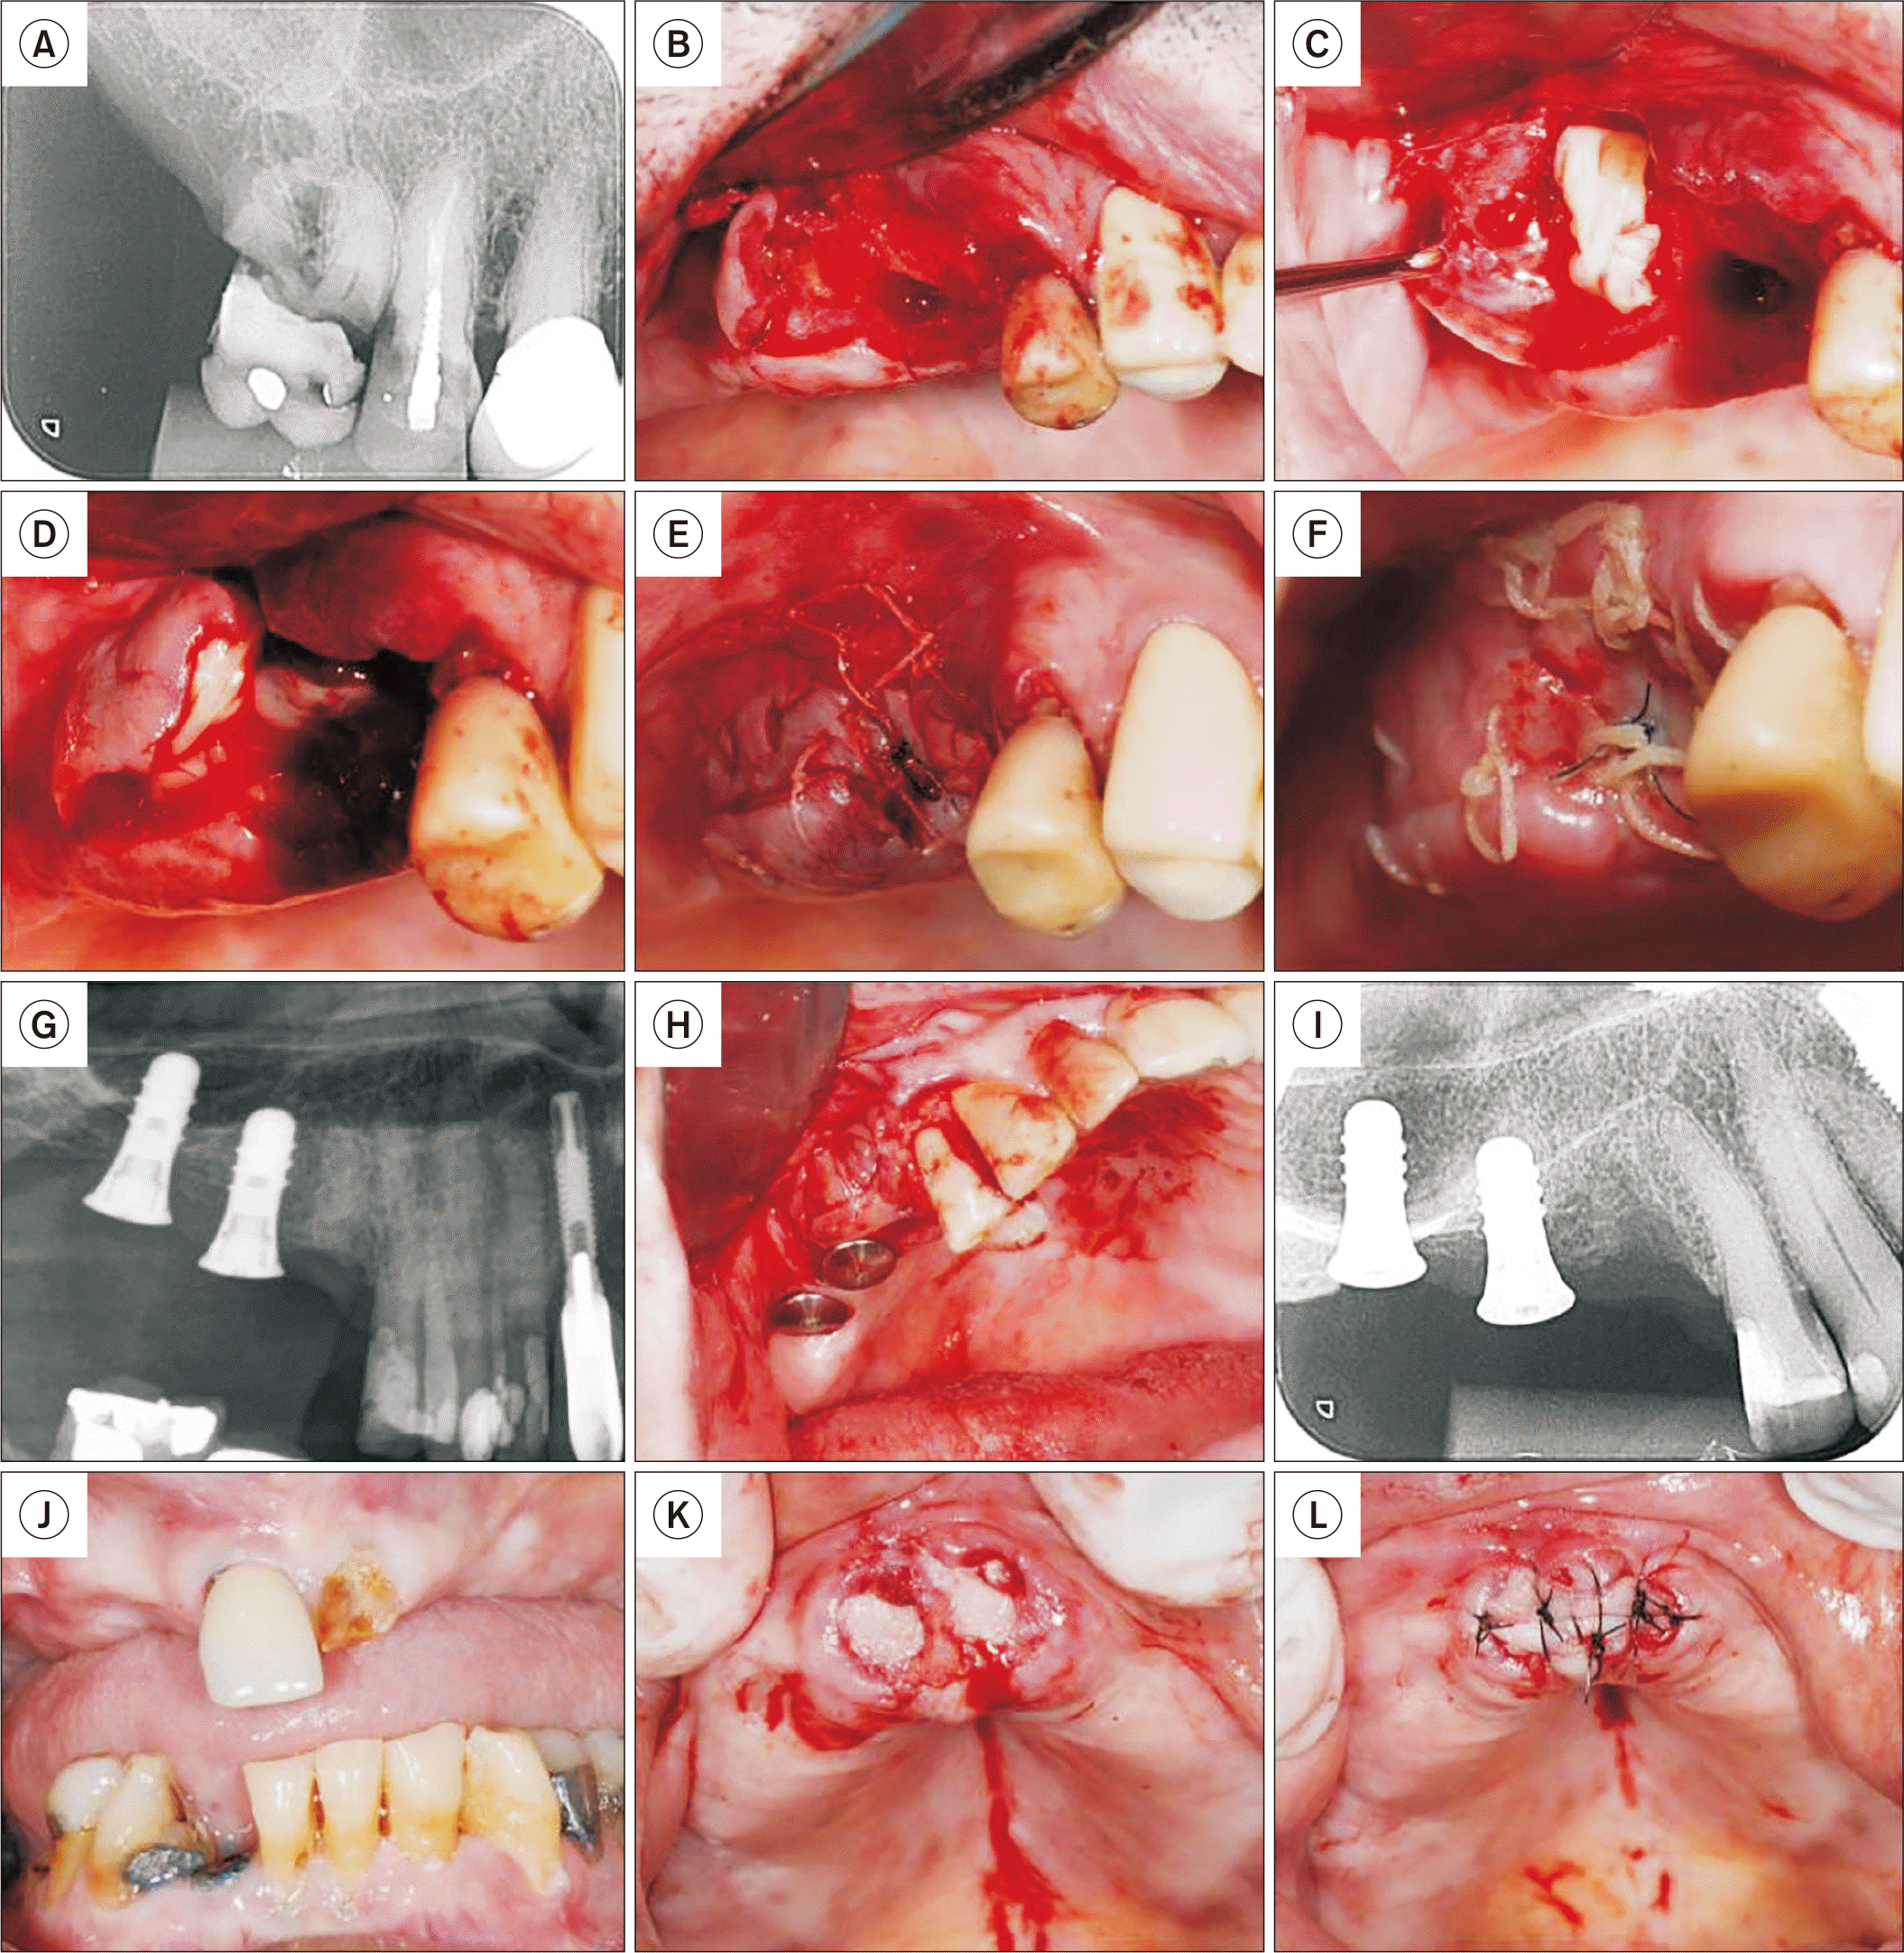

5. Bone socket preservation after tooth extraction

Patients requiring tooth extraction for future dental implant placement, with bone socket preservation using L-PRF, were indicated for this procedure. In Case 3 (Fig. 5. A-5. F), an elderly male patient presented with extensive coronal destruction of tooth 16, requiring extraction to proceed with implant treatment. In Case 4 (Fig. 5. G-5. I), an elderly female patient required the extraction of a residual root in the region of tooth 15, adjacent to previously placed implants, to continue with implant rehabilitation. In Case 5 (Fig. 5. J-5. L), an elderly male patient with a history of cancer treatment required the extraction of teeth 11 and 21. In all cases, following incision and flap reflection, extractions were performed using elevators. After cleaning the sockets, an L-PRF plug was inserted into each socket and covered with an L-PRF membrane. The surgeries were completed with sutures to secure the L-PRF in position. The patients presented absence of postoperative complications and satisfactory alveolar preservation for future rehabilitation.

Fig. 5

Bone socket preservation with leukocyte platelet-rich fibrin (L-PRF). A. Initial periapical radiograph of Patient 3, showing extensive coronal destruction of tooth 16. B. Following extraction, a sizable purulent collection was observed in the distal root area, which was curetted. C. An L-PRF plug and membrane were placed in the area that was curetted. D. An L-PRF plug and membrane were also placed in the mesial root area. E. Immediate suture. F. Clinical appearance 15 days post-extraction. G. Initial radiograph of Patient 4, showing a root remnant in the region of tooth 15, adjacent to implants. H. After root extraction, L-PRF membranes were positioned both in the alveolar area and around the neighboring implant. I. Immediate periapical radiograph post-extraction. J. Patient 5, with a history of cancer treatment, presenting teeth 11 and 21 indicated for extraction. K. L-PRF plugs positioned in each socket. L. L-PRF membrane sutured over the sockets. Note that exposure of the L-PRF membrane in the oral cavity does not pose any issues.